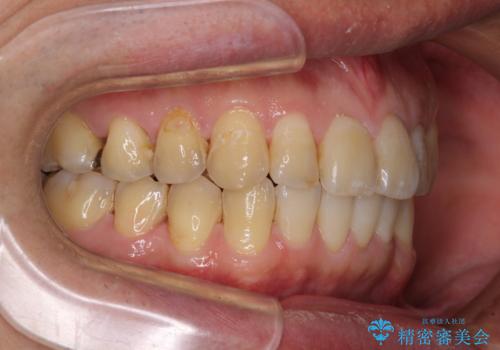

前歯のデコボコと下顎の八重歯 インビザラインによる矯正治療

- 前歯のデコボコや八重歯を気にして来院された患者様です。

インビザラインを用いて、歯列を整えることとしました。

下顎前歯は後戻りを起こしやすいため、舌側を細いワイヤーで固定し、マウスピース型リテーナーで保定を行うこととしました。